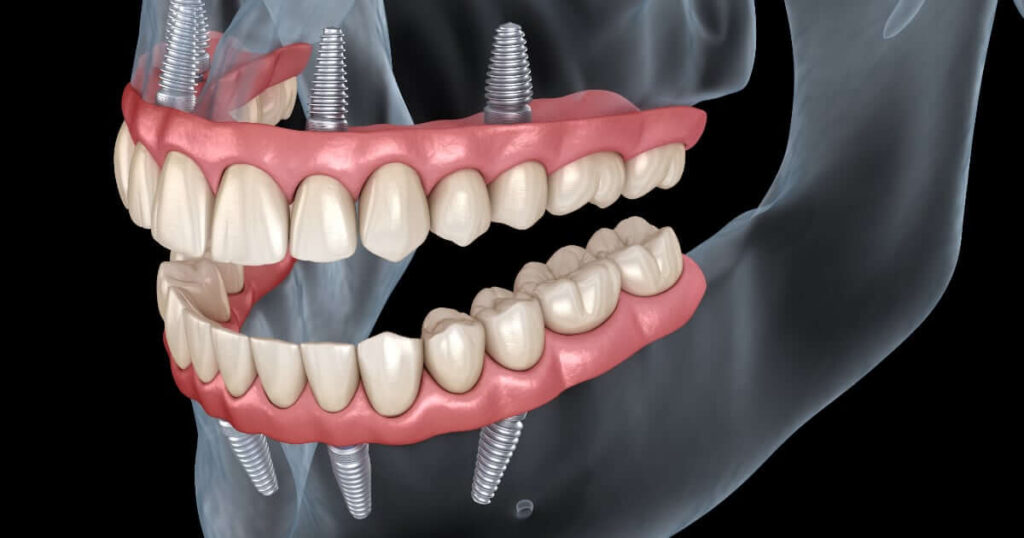

All-on-4 rehabilitation is one of the most advanced treatments in dentistry for patients who have lost all their teeth or are about to lose them. It allows you to recover a full set of fixed teeth with only 4 implants per arch, quickly restoring function and aesthetics. It’s a safe, comfortable, and long-lasting option that allows you to speak and eat with confidence again. It restores function, aesthetics, and confidence in a very short time.